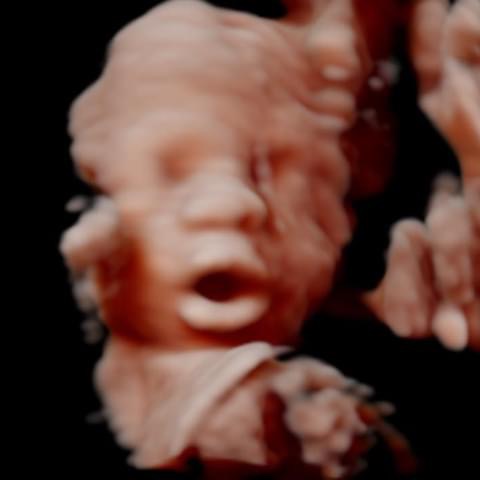

All photos are from our equipment and are of our actual clients.